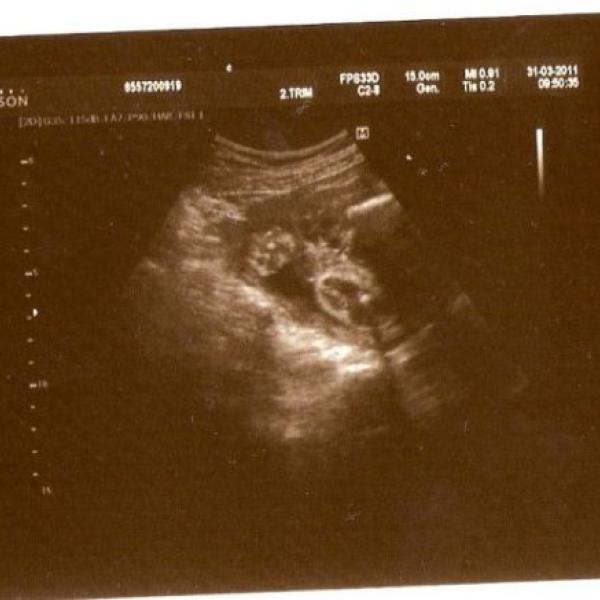

Myslíte si, že je to holčička nebo chlapeček? Nahoře je vidět ručička sevřená v pěst a pak nožičky a rozkrok.

Co myslíte bude to hočička nebo chlapeček? Nahoře je vidět ručička v pěst a pak nožičky a rozkrok.

Ahoj jsem tu nová, TP 28.6. Stále nevím, co se ukrývá v bříšku, paní doktorka si není jistá. Zkuste tipnout podle fota z ultrazvuku, měly by tam být nožičky a rozkrok.

Myslíte si, že je to holčička nebo chlapeček. Měla by to být fotečka nožiček a rozkroku, ale paní doktorka si stále není jistá, co to je.